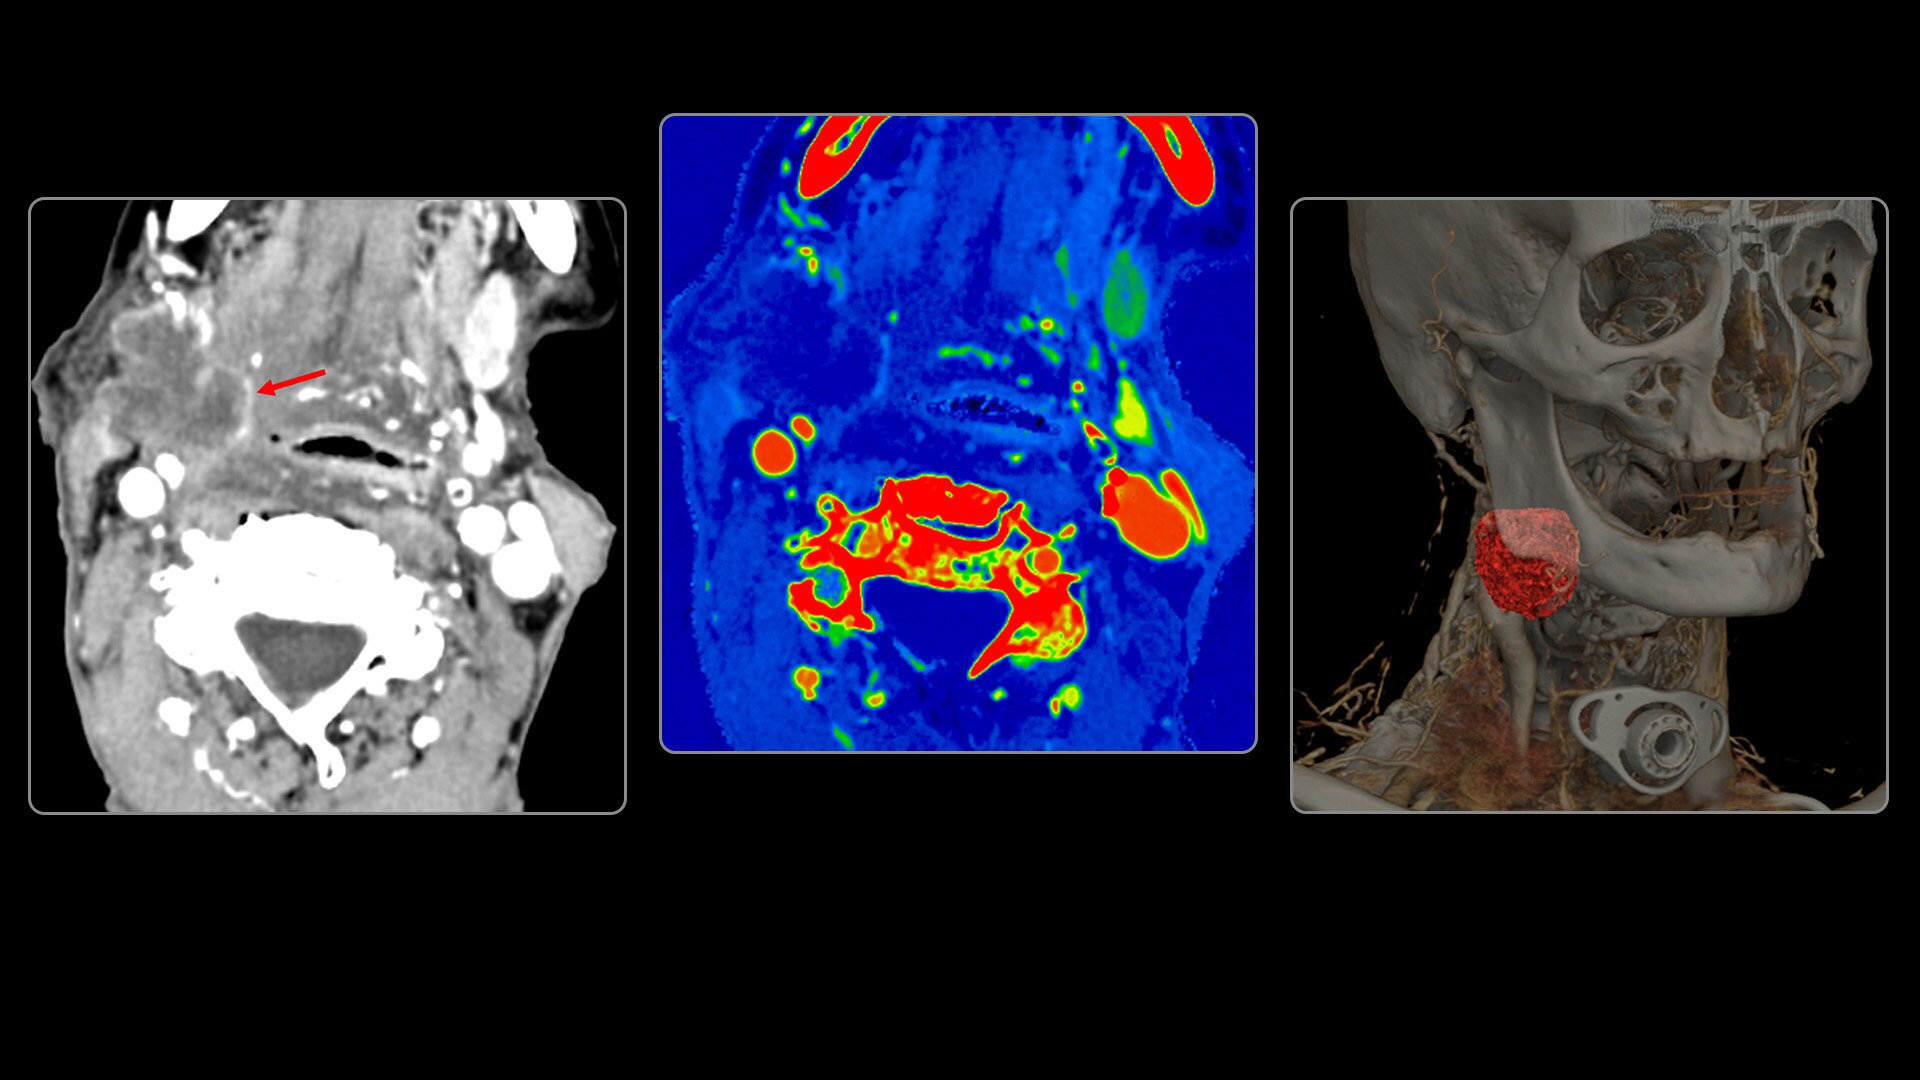

On-demand spectral imaging enabled by 8-energy bins

Our advanced spectral imaging capabilities are intended to allow you to experience the difference between seeing and knowing so you can confidently detect, characterize and monitor disease.

Photonova Spectra is also designed to enhance material separation for tissue characterization and disease quantification, bringing potentially greater diagnostic confidence in every acquisition across care areas.

A full range of spectral imaging series is generated natively on console and available for transfer to PACS. The full-fidelity spectral data acquisition is intended to provide native DICOM images and material maps to support clinical diagnosis, with improvements of up to 4x enhanced energy discretization1, 2x higher material map spatial resolution2, and 2x improved iodine detectability3.